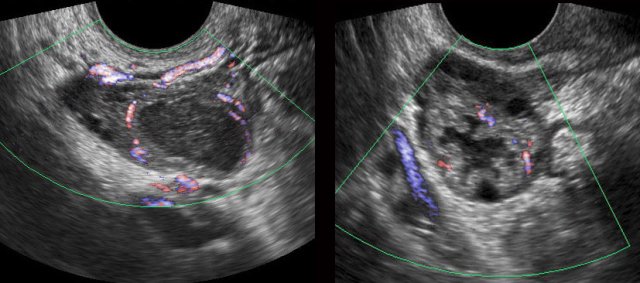

Pyosalpinx

case 1

these images are of a young woman with pain in the RLQ for two days and CRP 170 and WBC 14.

US respectively

TVUS shows tortuous, thick-walled tubular

structure right of the uterus (ut.), in combination with the CRP, typical for a

pus-filled Fallopian tube (pyosalpinx).

This

patient was successfully treated with antibiotics but had recurrent episodes.

For this reason she underwent

a tubectomy three years later.

case 2

Young lady with pain RLQ since three days. CRP 100 and WBC 23, suspect for appendicitis.

US shows

turbid peritoneal fluid and a dilated, thick-walled Fallopian tube, filled with debris. Complete cure after antibiotics.

case 3

Young woman with acute pain RLQ and a CRP 180, suspect for appendicitis.

US

confirms a IUD in the uterus and a large, right-sided pyosalpinx.

Complete

recovery after antibiotics and removal of the IUD.